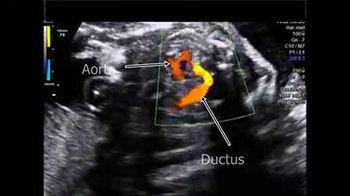

Challenge your diagnostic skills: Anything notable in these images of a fetal heart?